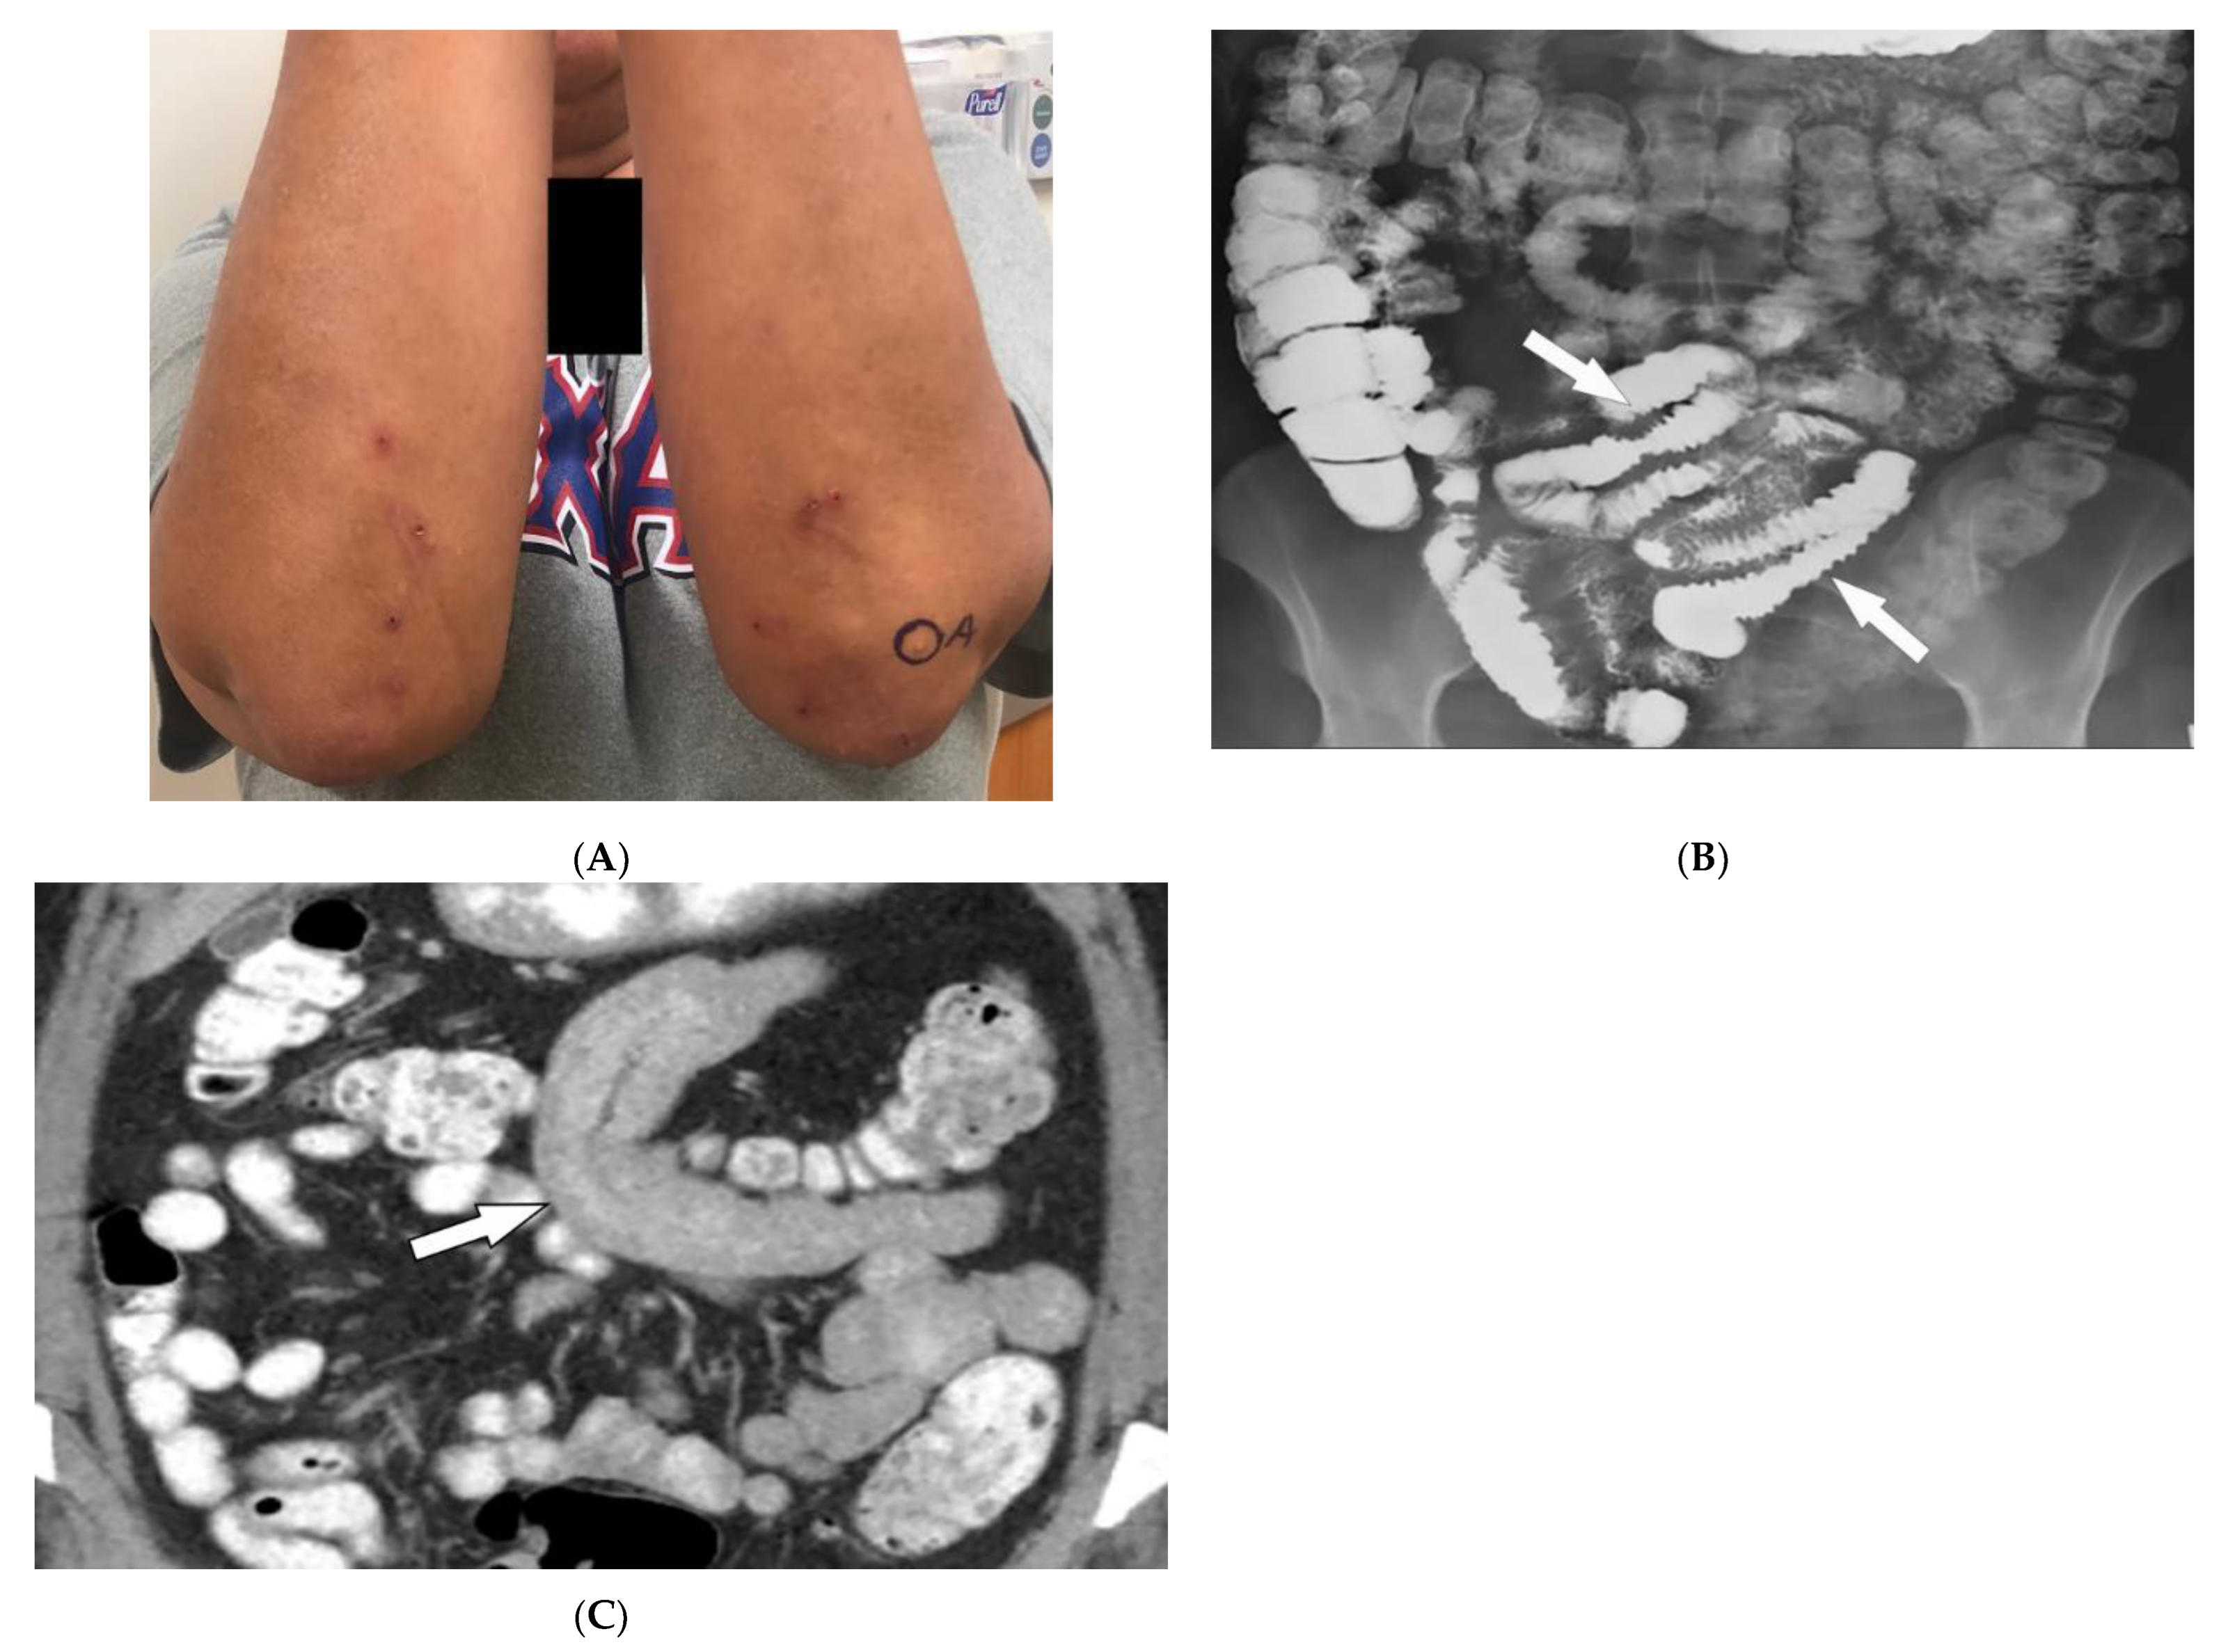

2.4. Celiac Disease

| Celiac disease | Dermatitis herpetiformis Psoriasis Intestinal manifestations | Small-bowel dilation Reversal of jejunal and ileal folds |